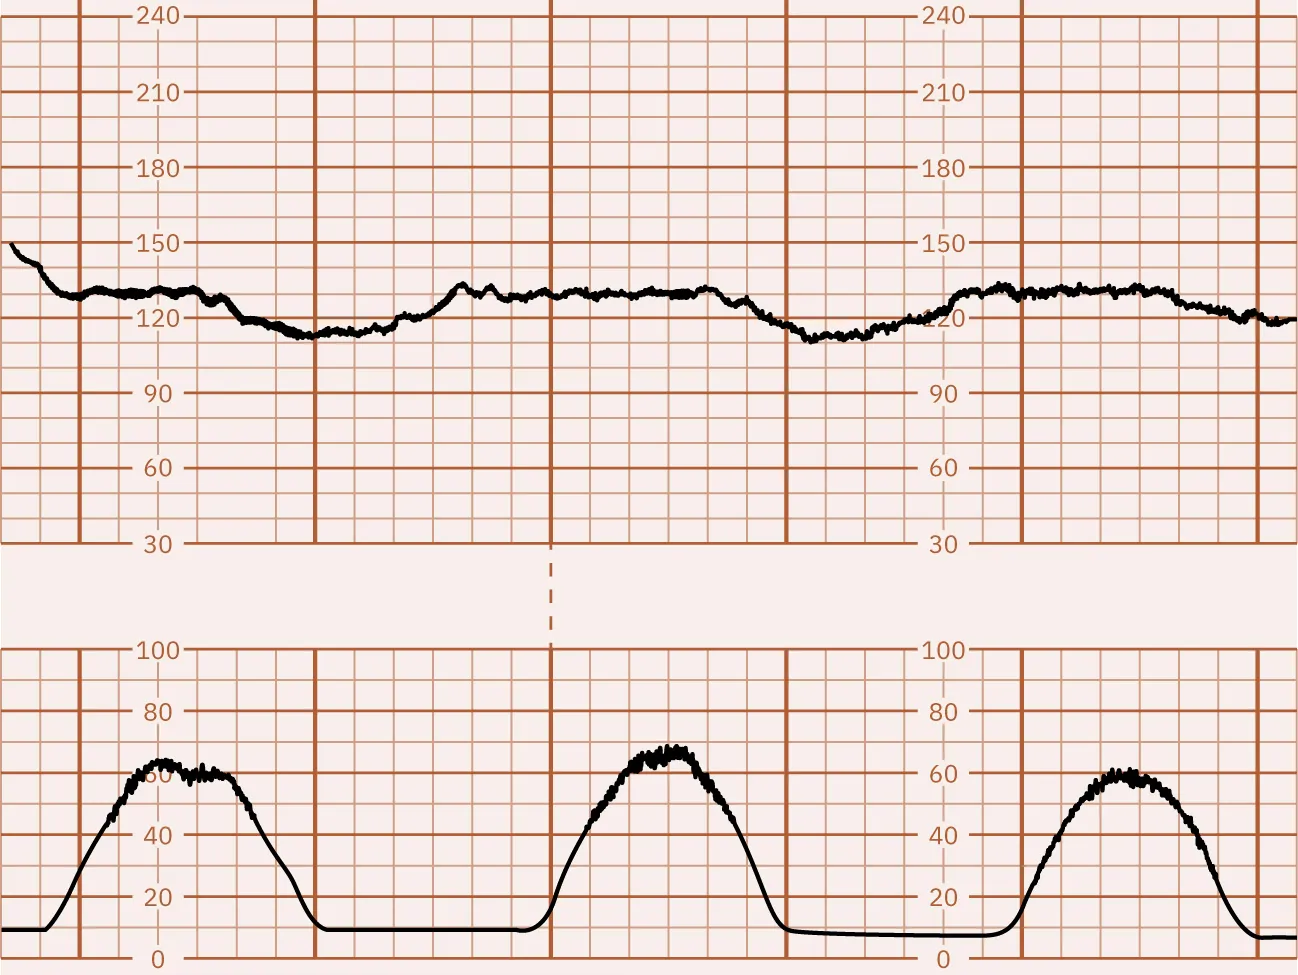

Describe the periodic changes in this monitor strip. Are they reassuring or nonreassuring?

Copyright Rice University, OpenStax, under CC BY 4.0 license

Explain how this monitor tracing shows adequate fetal oxygenation.

The nurse interprets the following external EFM tracing.

How does the nurse document the summary of this tracing?